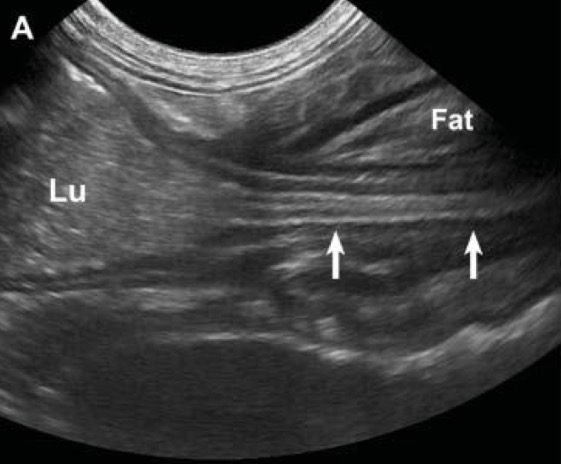

What organ is prominent in this ultrasound?

Hyper-echoic cortex and medullary rim sign

What anomalies are occurring in this kidney